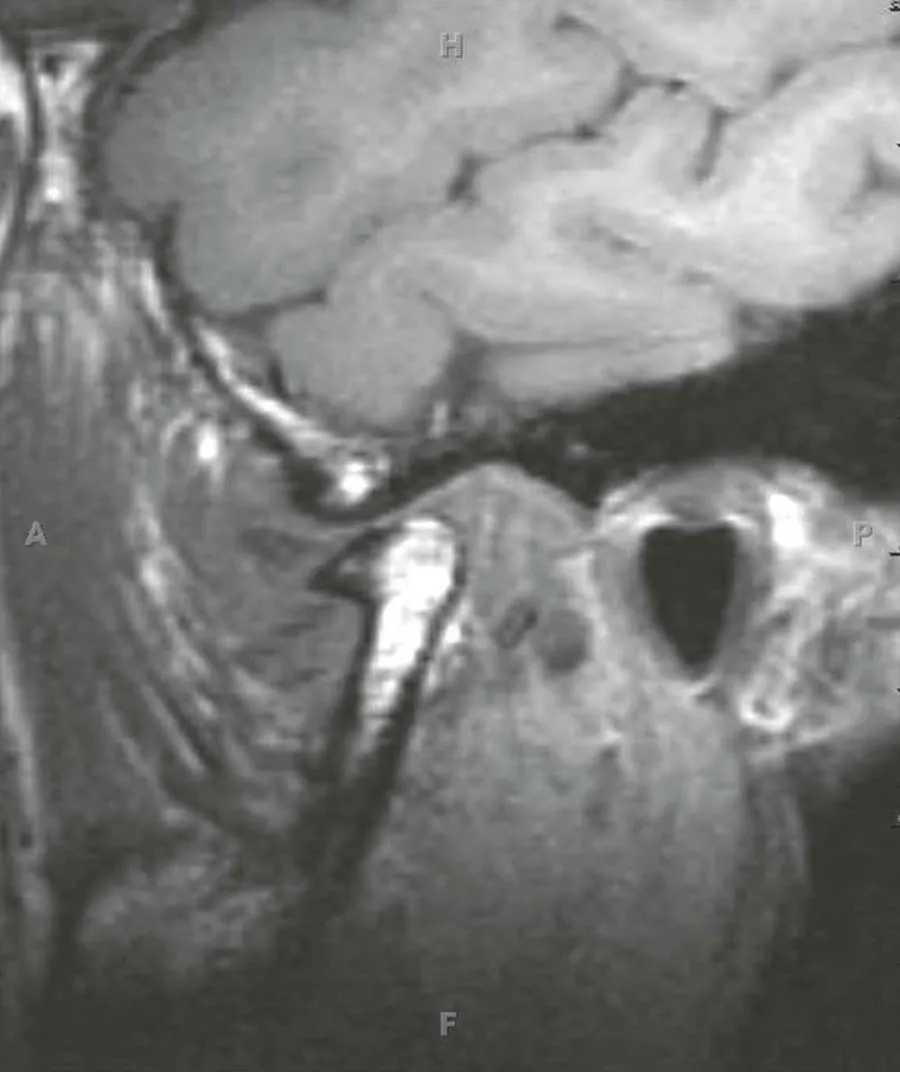

Incorporate today's most advanced imaging techniques with the new 4th edition of Head and Neck Imaging! A bestselling volume in the popular Case Review Series, this updated reference helps speed your differential diagnoses and ensure your proficiency, in addition to serving as a study guide for general radiology and neuroradiology subspecialty examinations, certificates of added qualification, and radiology/neuroradiology recertification. The all-inclusive volume can serve as a comprehensive review of the subspecialty and as a primer for excelling at the Head and Neck Tumor Boards.- Efficiently study and review with help from a format that mimics the General Diagnostic Radiology and Neuroradiology Board Exams. Each case begins with a differential diagnosis question and follows with multiple-choice questions, answers with rationale, and an emphasis on clinical issues.- Explore hot topics including CT and MR angiography of the neck; multi-detector CT with 3D reconstructions; post-transplant lymphoproliferative disorders; HIV infections; squamous cell carcinoma, diagnostic and therapeutic image-guided procedures; medical economics; and much more.- Master the latest techniques with 150 new and 50 updated head and neck cases and over 800 images focusing on differential diagnosis, tumor staging, treatment options, and resectability issues.- Enhance your understanding with multiple-choice questions accompanying each case, emphasizing cranial nerves, skull base lesions, sinonasal, orbital, salivary gland, aerodigestive system mucosal lesions and deep space neck masses.- Utilize convenient cross-references to recent articles.- Stay abreast of the most recent discoveries in HPV (+) squamous cell cancers, high-resolution imaging, and CTA, MRA, and CISS applications.- Explore the differential diagnosis and/or anatomic details of every case presented.- Understand the surgical and radiation therapy considerations for cosmetic and functional outcomes.- Expert Consult eBook version included with purchase. This enhanced eBook experience allows you to search all of the text, figures, and references from the book on a variety of devices.